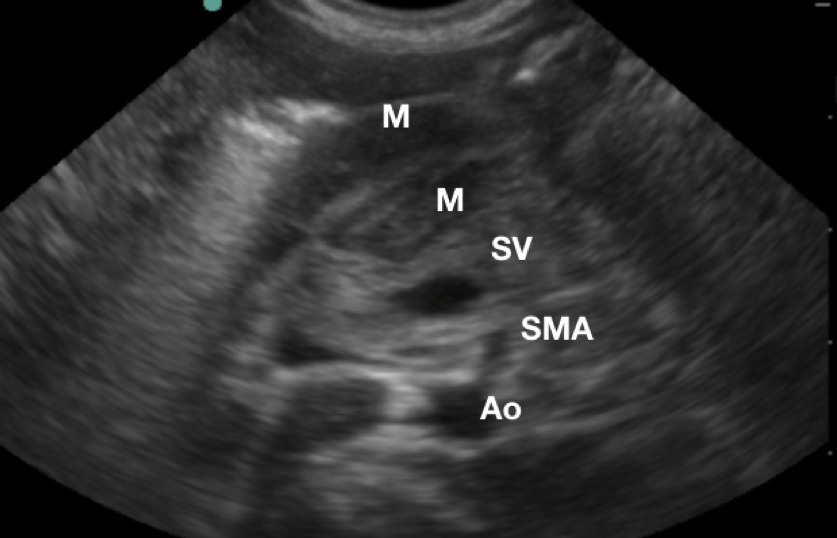

- Use the aorta/ superior mesenteric artery as additional landmarks if necessary (pylorus is anterior to them).

- Figure 3.Sonogaphic anatomy of the pyloric muscle (M) in relation to the aorta (Ao), superior mesenteric artery (SMA), and splenic vein (SV)